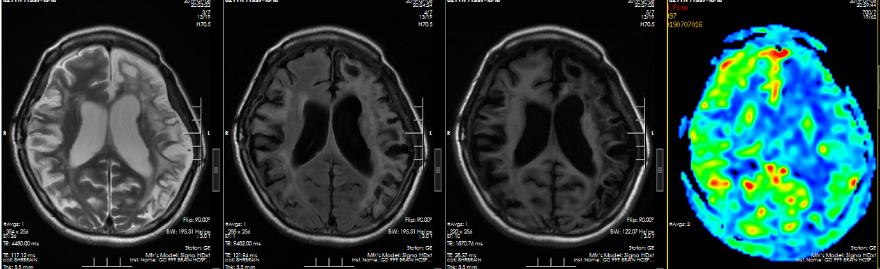

▲左侧脑血管重建术后3个月复查

仔细考虑之后,佳佳决定先接受左侧脑血管重建术(脑-硬脑膜-动脉-颞肌血管融合术)。术后回家休养了3个月后,佳佳遵医嘱到院复查。复查ASL序列提示右侧大脑半球、左侧额顶叶仍示多发片状低灌注区,左侧额颞岛叶灌注较前增高、明显代偿;DSA提示右侧颈外动脉向颅内无代偿,左侧颈外动脉向颅内代偿明显,颅内供血增加。

▲双侧脑血管重建术后一年复查

这次到医院复查,佳佳的精神状态非常好,让人很难把眼前这个开朗明媚的女孩与一年前那个病态十足的患者联想起来。复查影像提示:双侧脑血管重建术后,双侧颞浅动脉脑膜副动脉经软膜向颅内动脉吻合代偿。这下,佳佳一家总算是可以放心了。